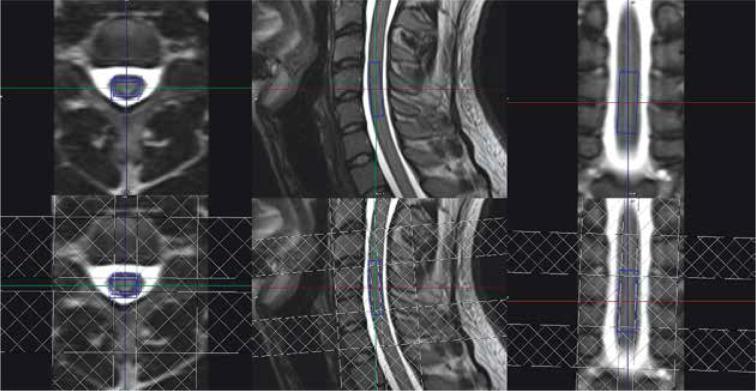

H-magnetic resonance spectroscopy (H-MRS) is a non-invasive technique that provides information on tissue metabolism and biochemistry. Because of technical difficulties, this method is rarely used in spinal cord examination. The main goal of this study was to develop a routine protocol for MRS of intramedullary lesions.

MATERIAL AND METHODS

A H-MRS protocol was set on a group of healthy volunteers. Forty-eight spectra were acquired in total. Thirty of them were acquired in cervical spinal cord, and the remaining 18 spectra were acquired in the thoracic spinal cord.

RESULTS

In H-MRS of the spinal cord one of the most important problems is small voxel size. Mean voxel size in this study was 7 × 9 × 29 mm, which is much smaller than in brain examinations. Finally, almost 60% of spectra were of acceptable quality in volunteer examinations, which enabled the subsequent examinations.

氢磁共振波谱(H-MRS)是一种提供组织代谢和生物化学信息的非侵入性技术。由于技术难题,该方法在脊髓检查中很少使用。本研究的主要目的是制定一种用于髓内病变磁共振波谱检查的常规方案。

材料与方法

为一组健康志愿者制定了H-MRS方案。共采集了48个波谱。其中30个在颈髓采集,其余18个波谱在胸髓采集。

结果

在脊髓的H-MRS检查中,最重要的问题之一是体素尺寸小。本研究中的平均体素尺寸为7×9×29毫米,远小于脑部检查中的体素尺寸。最后,在志愿者检查中,近60%的波谱质量可接受,这使得后续检查得以进行。